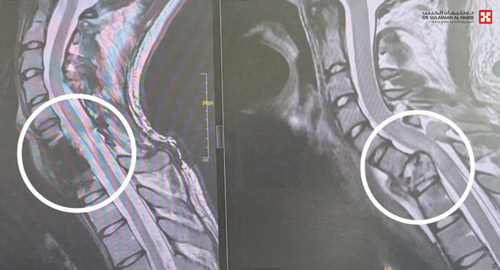

وقد أظهرت الأشعة وجود كسر مركب بالفقرة العنقية رقم «7»، وانزلاق غضروفي حاد وضغط على النخاع الشوكي، مع شلل في الأطراف العلوية ابتداءً من العصب رقم «7» وإلى الأسفل. وقد أجريت له عمليتان؛ تم في الأولى إزالة الفقرة العنقية السابعة المتهشمة بالكامل، والاستعاضة عنها بأخرى صناعية وتثبيتها بصفيحة وبراغي، في تدخل طبي نادر حيث تم الدخول من الجهة الأمامية، واستمرت العملية لـ«5» ساعات، وأعيد إلى العناية المركزة ووضع على التنفس الاصطناعي.

وبعد مرور «72» ساعة وتحسن حالته، نقل الشاب إلى غرفة العمليات مجدداً، وخضع لعملية جراحية أخرى استمرت «3» ساعات، وتم فيها إزالة الكسور المتبقية خلف العمود الفقري، وكذلك تحرير النخاع الشوكي من الضغط، وتثبيت العمود الفقري ببراغي وقضبان معدنية من الفقرة العنقية 5 و6، على الفقرة الصدرية 1 و2. وقد تم الدخول في هذه المرة من الخلف. وبعد العملية نقل الشاب مجدداً إلى العناية المركزة ووضع على التنفس الاصطناعي لمدة «48» ساعة.